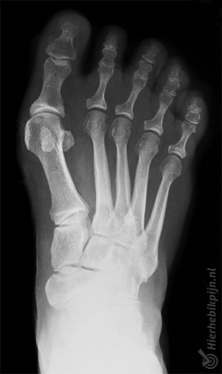

Hallux valgus (juanete) Posición anormal del dedo gordo

El hallux valgus es una afección que consiste en una desviación del dedo gordo del pie en dirección a los demás dedos. El hueso metatarsiano que se encuentra justo antes del dedo gordo se gira en la otra dirección (hacia fuera). El resultado es una protuberancia en la parte exterior del dedo gordo. Esto se denomina "juanete".